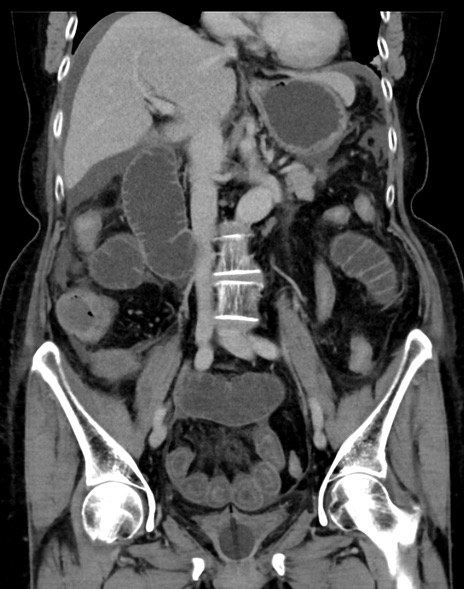

症例13 CT(冠状断像)1日半後

(横断像)1日半後